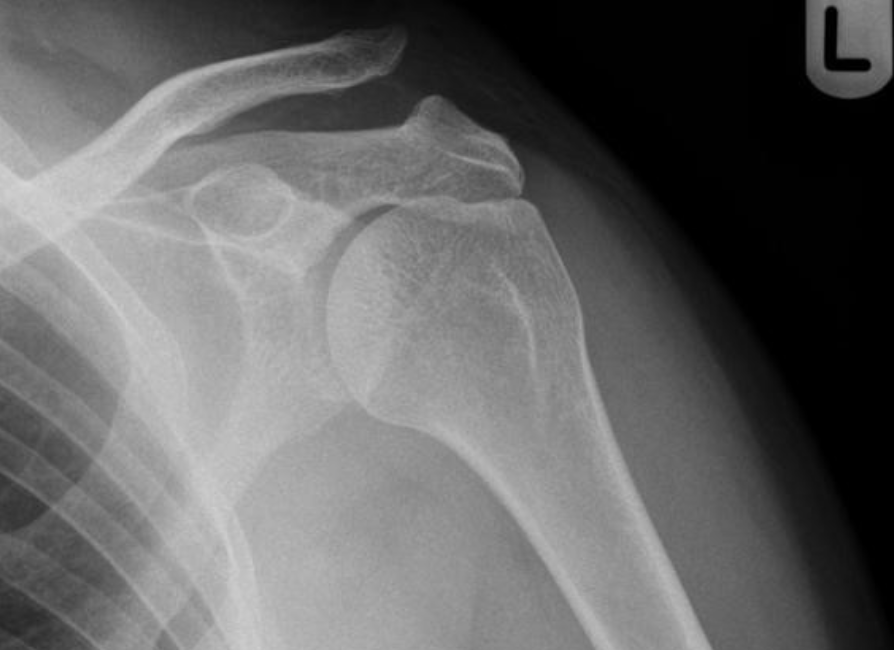

Left Acromio-clavicular joint dislocation

1. Short term use of a sling for pain relief

2. Referral for physiotherapy to start early ROM to maintain left shoulder function

3. Simple analgesia

4. Ice the left shoulder for 48-72 hours following injury